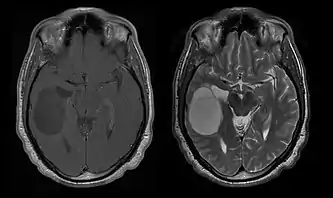

La tomodensitométrie (TDM) et L'imagerie par résonance magnétique (IRM) peuvent détecter efficacement une néoplasie dans le cerveau. L'IRM est plus sensible que la TDM pour identifier les lésions, mais présente des contre- indications pour les patients porteurs de stimulateurs cardiaques, de prothèses incompatibles, de clips métalliques et contre-indications. La TDM reste la méthode de choix pour détecter les calcifications au sein des lésions ou les érosions osseuses de la calotte ou de base du crâne. L'utilisation d' agents de contraste, iodés dans le cas du scanner et paramagnétiques (gadolinium) dans le cas de l'IRM, permet l'acquisition d'informations sur la vascularisation et l'intégrité de la barrière hémato-encéphalique, une meilleure définition de la tumeur tumorale par rapport à l' œdème environnant et à la génération d' hypothèses sur le degré de malignité. L'examen radiologique permet également d'évaluer les effets mécaniques et les modifications importantes des structures cérébrales résultant de la tumeur, telles que l' hydrocéphalie et les hernies, dont les effets peuvent être fatals. Enfin, en préparation à la chirurgie, ce diagnostic peut être utilisé pour déterminer la localisation de la lésion ou l'infiltration de la tumeur dans des zones vitales du cerveau. À cette fin, l'IRM est plus efficace que la tomodensitométrie car elle peut fournir des images en trois dimensions.

Les outils d'imagerie radiologique diagnostique mettent en évidence la modification du tissu néoplasique par rapport au parenchyme cérébral normal (par le biais de modifications de la densité tissulaire imagée électroniquement en TDM et de l'intensité du signal en IRM). Comme la plupart des tissus pathologiques, les tumeurs sont également reconnaissables par une accumulation accrue d'eau intracellulaire. Dans la tomodensitométrie, ils apparaissent hypodenses, c'est-à-dire de moindre densité que le parenchyme cérébral, dans la tomographie par résonance magnétique nucléaire avec relaxation spin-réseau hypointense et en relaxation spin-spin ainsi que l' hypersignal en pondération protonique (PD).

La tomodensitométrie du cerveau montre généralement une masse tissulaire qui peut être améliorée par l'un ou l'autre contraste. Au scanner, les gliomes de bas grade apparaissent généralement isodenses au parenchyme normal et peuvent donc ne pas présenter de rehaussement de contraste. De même, les lésions de la fosse crânienne postérieure sont difficiles à identifier au scanner. Par conséquent, les seuls résultats d'une telle tomographie ne sont pas toujours suffisants à des fins diagnostiques. Dans les cas douteux, l'utilisation de l'imagerie par résonance magnétique plus sensible est indispensable.

Sur-L'IRM montre une tumeur intracrânienne comme une lésion massive qui peut devenir plus luminescente après utilisation du produit de contraste. Cependant, il y a toujours une anomalie de signal dans -L'imagerie par résonance magnétique, qui indique la présence d'une néoplasie ou d'un œdème vasogénique. Habituellement, une luminescence accrue (amélioration du contraste) indique une tumeur d'un grade supérieur de malignité. Un anneau de contraste est caractéristique du glioblastome, avec la partie luminescente correspondant à la partie vitale de la tumeur maligne, et la plus foncée - zone hypointense correspondant à une nécrose tissulaire.

Les patients souffrent d'une variété de symptômes caractéristiques d'une lésion massive focale ou multifocale. L'IRM montre généralement des tumeurs avec un rehaussement de contraste homogène au sein de la substance blanche périventriculaire profonde. La multifocalité et le rehaussement inhomogène sont typiques des patients dont le système immunitaire est affaibli. L'analyse du lymphome du SNC est extrêmement importante dans le diagnostic différentiel de la néoplasie cérébrale. Il est à noter que l'administration de corticoïdes peut entraîner la disparition complète du rehaussement, rendant difficile le diagnostic des lésions. Par conséquent, si un lymphome du SNC doit être pris en compte dans le diagnostic différentiel, les corticoïdes doivent être évités à moins que l'effet de masse ne provoque un problème grave et immédiat chez le patient.

Des progrès significatifs ont récemment été réalisés dans le diagnostic et le traitement de ces lésions, entraînant une amélioration de la survie et du contrôle des symptômes. L'apparition des signes et des symptômes est similaire à celle d'autres lésions massives du cerveau. La méthode de diagnostic de choix est l'imagerie par résonance magnétique utilisant des produits de contraste.